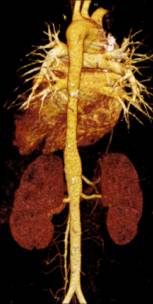

Компьютерная

томография: гипоплазия (тубулярное сужение от уровня перешейка до диафрагмы)

нисходящей грудной аорты с максимальным сужением до 6 мм в средней трети, кальцинатами стенки в этой

области.(рисунок 1)

Рисунок 1. КТ-АГ аорты

при гипоплазии нисходящей грудной аорты

А. 3D реконструкция В. Аксиальный срез с участком кальциноза

аорты